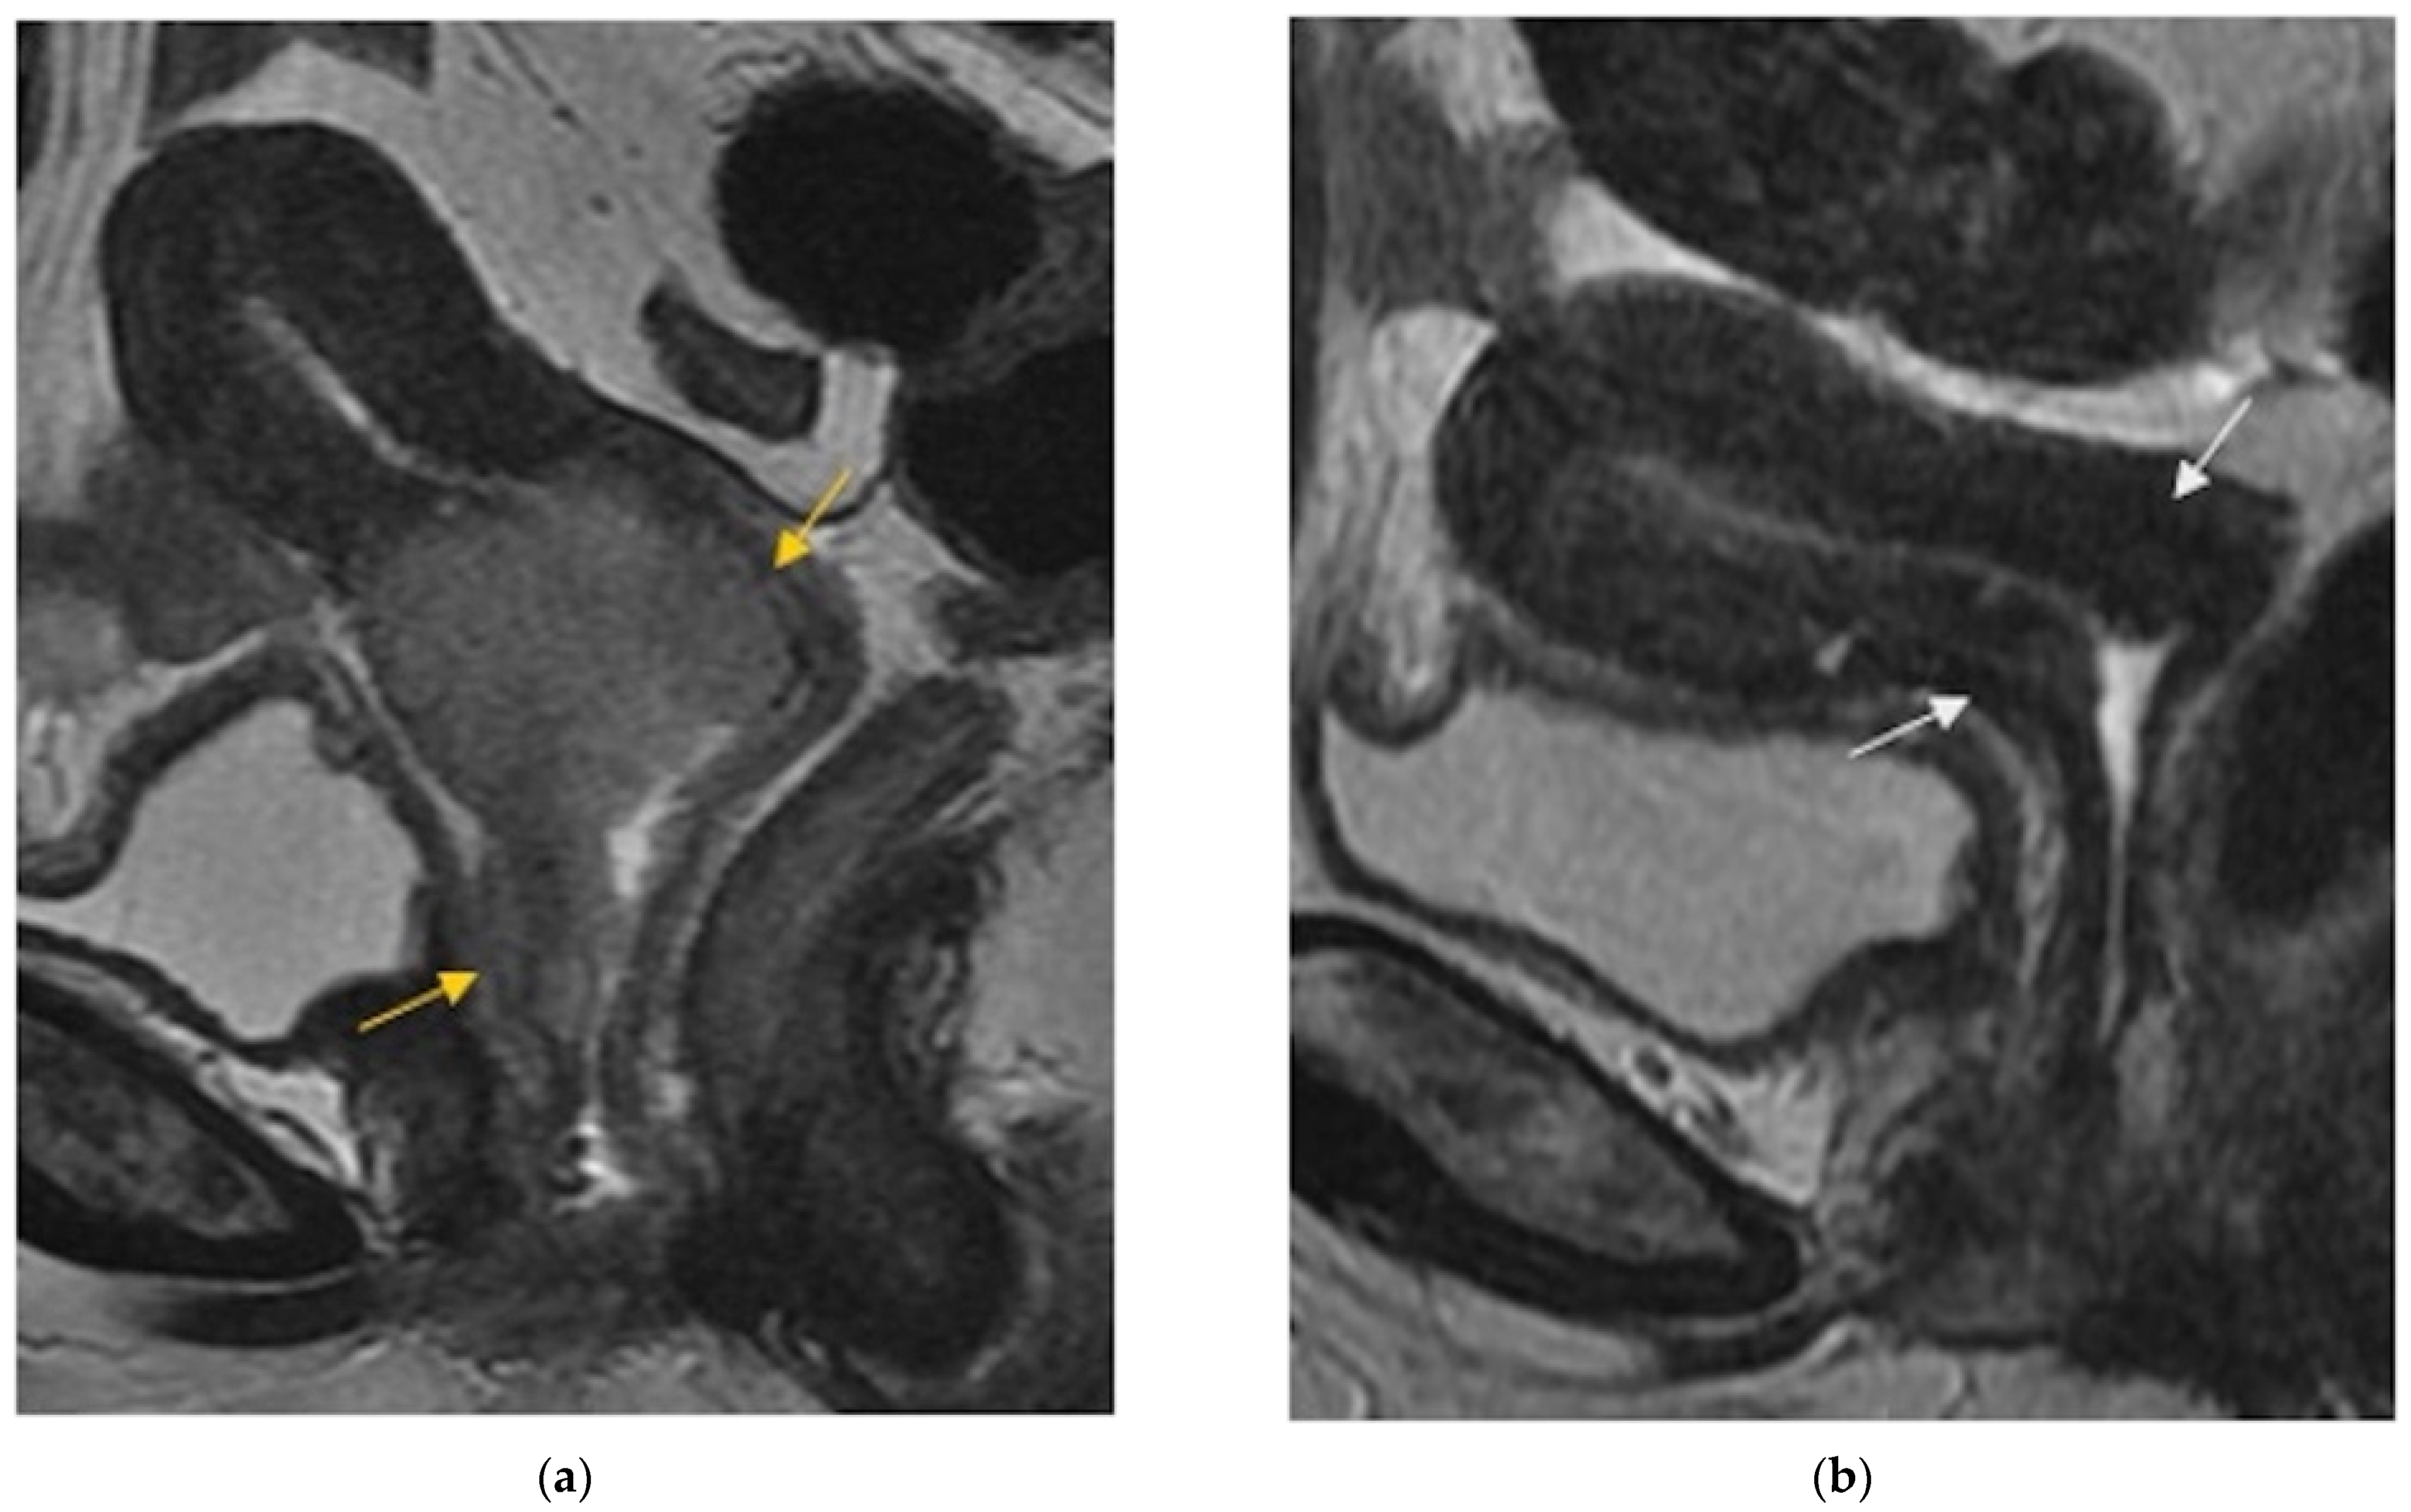

| Local | |

Cervix, parametria, or vaginal cuff![]() |